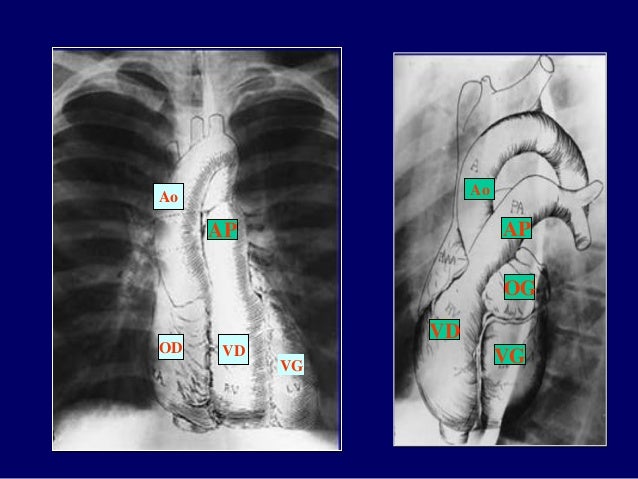

17. 17. OD VD VG Ao AP Ao VD OG VG AP

31. 31. Ao AP VD OG VG

33. 33. Tim và mạch máu trung thất Động mạch chủ lên Tĩnh mạch chủ trên Động mạch phổi Thất phải Động mạch chủ xuống Thất trái